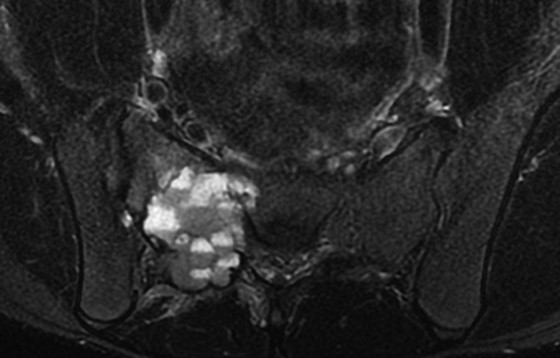

• CT

• STIR

• 左:CT(骨条件)、右:造影CT

• T1WI、T2WI、Gd-T1WI